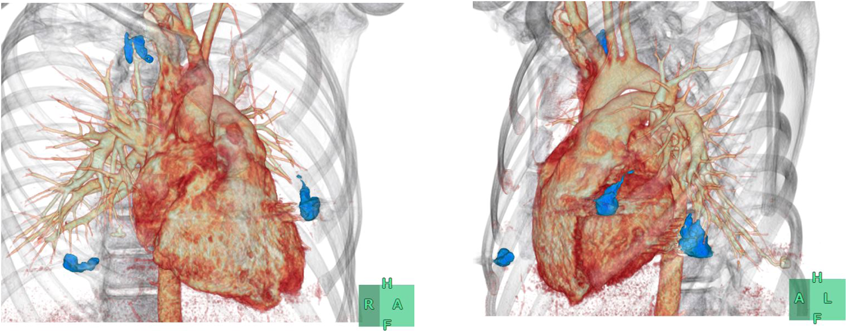

Pediatric Cardiology and Cardiac Surgery 33(3): 241-246 (2017)

Fig. 4 The Reperfusion of PAVMs and the regrowth of untreated PAVMs were not identified in follow-up CT performed at six months after embolization

Embolic coil presents a blue image. Draining veins have disappeared.